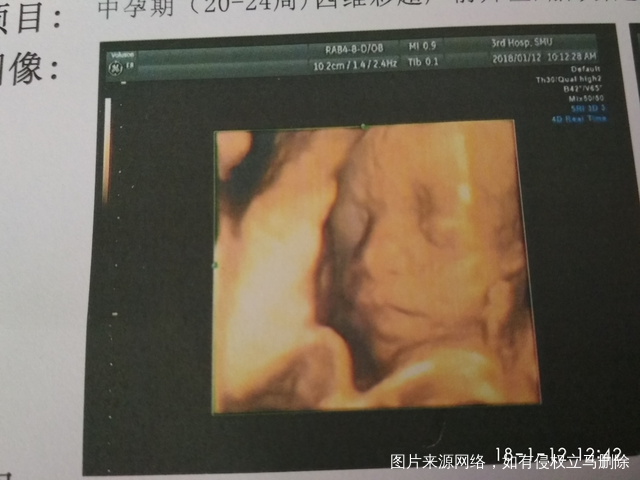

今天早早起床吃饱喝足,要去做四维了,起床就交代小宝就听话多动动。等了三个多小时才到我,因为前面三个人做的都很慢,反反复复要复查,出去爬楼梯又吃东西的,都还没做成功。[鼓掌]到我的时候半个小时就做好了,做到一半时医生说这个宝宝不配合怎么做呀,我心里就默默的叫了好几声小宝你配合动动呀,没多久就做好了[大笑]]原来他在等妈妈的发号才能动[偷笑][偷笑]这是图片,我觉得除了鼻子像我以外其他都不知道像谁了[勉强]宝妈帮忙看看男宝还是女宝啊[大笑][大笑][大笑]也祝你们顺顺利利四维彩超通过!!!!